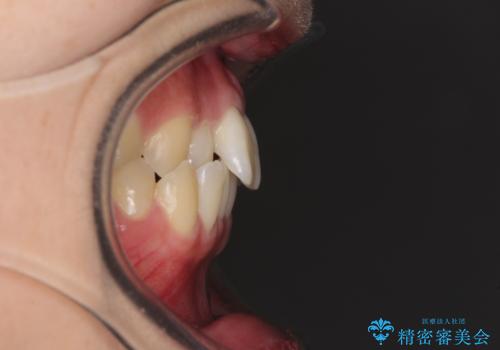

- 前歯のクロスバイトを気にして来院され患者様です。

治療期間が世界的な感染症の流行時期と重なったため、海外と日本での往来が困難となり、治療継続が懸念されました。

それでも、しっかりとマウスピースを装着してくださったので、大きなトラブルもなく治療を終えることができました。